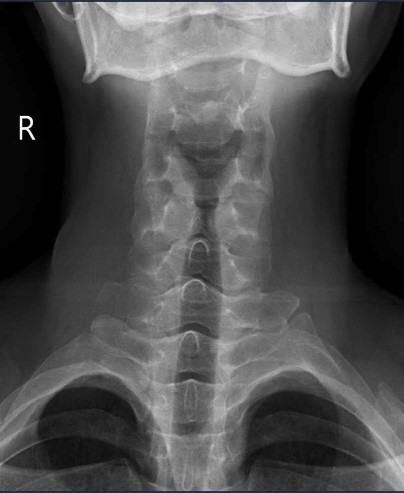

- X-quang cột sống cổ: Hình ảnh bình thường, chưa thấy tình trạng dính khớp hay gai xương.

Hình ảnh XQ cột sống cổ bình thường